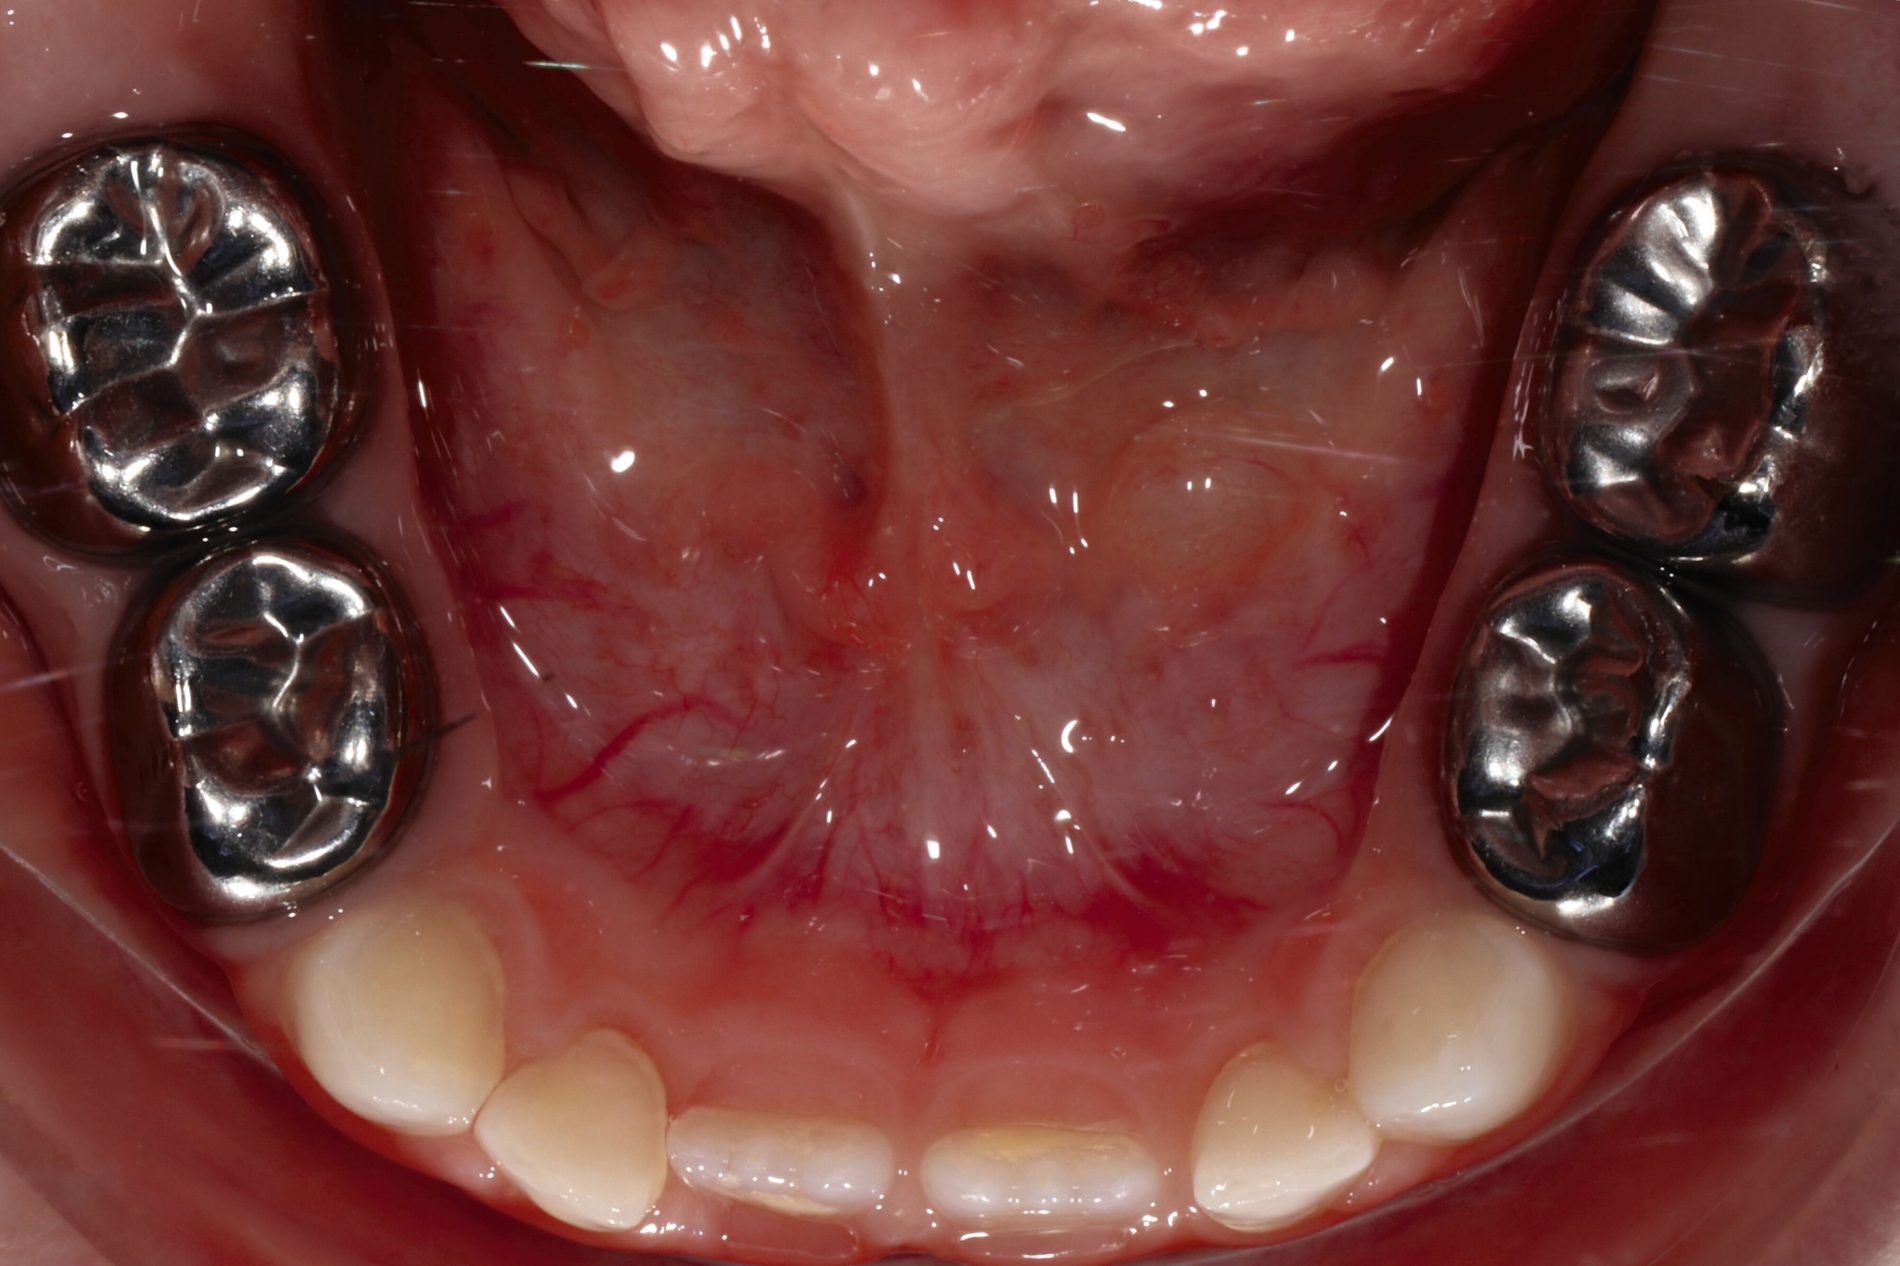

Karies an Milch- und bleibenden Zähnen stellt ein chronisches Ungleichgewicht mit überwiegendem Mineralverlust dar. Daraus ergibt sich eigentlich schon die Richtung einer ursächlichen Therapie: die Umkehrung zur Remineralisation. Dies bietet sich gerade bei kleinen Kindern mit Milchzähnen an, die dann später ohne zwingende Notwendigkeit einer restaurativen Therapie exfoliieren können. Die Läsionen können „einfach“ inaktiviert werden, was durch eine verbesserte tägliche Mundhygiene und durch Fluorideinsatz sehr wirkungsvoll erzielt werden kann (Abbildung 1).

(Häusliche) Kariesinaktivierung

Die (häusliche) Kariesinaktivierung bietet hier einen biologischen, ursächlichen Ansatz: Gerade bei offenen, kariösen Defekten ohne irreversible pulpale Schädigung kann sie zum Beispiel bei jüngeren Angstpatienten als non-invasive Kariestherapie ohne Bohrer [Santamaria et al., 2015], Zange oder gar Narkose dienen [Hansen und Nyvad, 2017]. Dabei sind regelmäßige Mundhygienemaßnahmen und eine risikogerechte Zufuhr an Fluoriden essenzielle Bausteine der Therapie (Abbildung 1).

Die zentrale Zielsetzung dieser Kariestherapieoption (Kariesinaktivierung) besteht folglich darin, das chronische Ungleichgewicht durch eine Reduktion der Demineralisationsfaktoren und eine Verbesserung der Remineralisation zu kompensieren, was die Eltern durch das Nachputzen der Kinderzähne mit fluoridhaltiger Zahnpasta selbst durchführen. Eigene Auswertungen haben gezeigt, dass die häusliche Kariesinaktivierung kombiniert mit regelmäßigen Fluoridlackapplikationen in der Praxis selbst bei Kariesrisikokindern genauso erfolgreich war wie die approximale Kompomerfüllung [Santamaría et al., 2018], was sich mit der internationalen Literatur deckt [Peretz und Gluck, 2006; Schmoeckel et al., 2020].